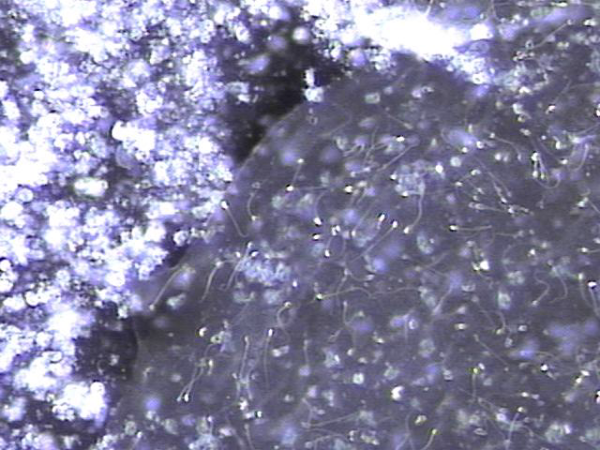

주2회 전립선의 표적 치료후 탈락된 상피세포 덩어리와 염증세포들입니다.

"Desquamated epithelial cell clusters and inflammatory cells after twice-weekly targeted prostate therapy."